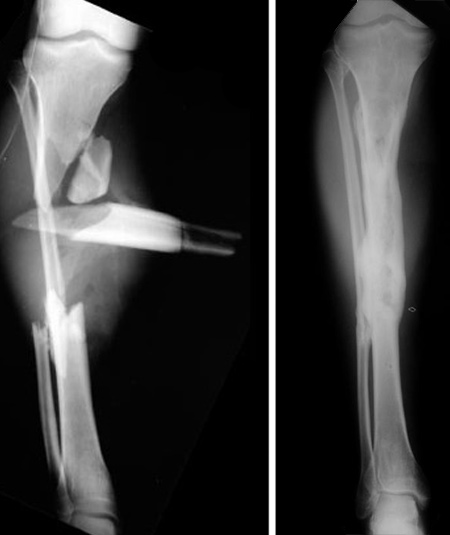

This is usually caused by a broken bone piercing the skin during a high-impact trauma, and it most commonly affects the lower leg, but it can occur in any part of the extremities.

Although any bone can experience an open fracture, the tibia, or shin bone, is the most susceptible. This is because a substantial portion of the tibia is immediately beneath the skin rather than having surrounding muscles like the femur (thighbone). When the tibia breaks, it can easily protrude through the thin layer of skin. When other bones that are better surrounded by soft tissues experience open fractures, it is usually because of a high energy injury mechanism such as a high-speed car crash or a fall from a substantial height.

Unless there are other emergency procedures that must be performed, such as fasciotomy for compartment syndrome, this acute wound care will be followed by surgical realignment of bones. The fracture is either temporarily or definitively stabilized at this initial operating room setting. This typically involves open reduction (making an incision to access and realign the bone or bones manually), followed by internal or external fixation.

Fixation refers to the use of rods, wires, pins, screws and/or plates placed to hold the bone in proper position during healing. Depending on the severity of the wound, additional procedures for wound management (additional cleaning and/or skin or muscle grafts to cover the wound) may be required.